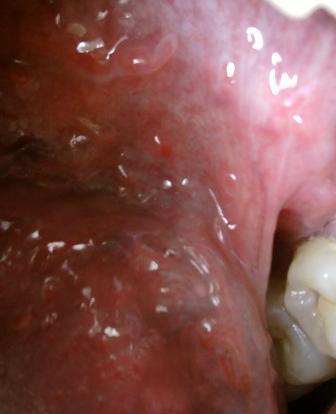

石家庄九州皮肤病医院 > 尖锐湿疣 > > > 肛门尖锐湿疣还能治愈吗尖锐湿疣发病部位是比较隐蔽的,其中生殖器官周围,肛门周围,口腔周围等等是尖锐湿疣的常发部位。因此患病之后及时去正规的医院进行治疗很关键。

肛门尖锐湿疣还能治愈吗要想尽早治愈,一定要稳定好心态,及时接受救治才能早日康复。早期病情发展较慢,有三个月左右的潜伏期,病毒扩散较慢,这是治疗的最佳时期。想要更好的治愈疾病,在平时应该及时做好必要的防护工作,平时养成良好的生活习惯,注意个人卫生,尖锐湿疣病毒具有很强的传染性,其中直接接触传染,间接接触传染和母婴传染是尖锐湿疣病毒传播的主要途径。